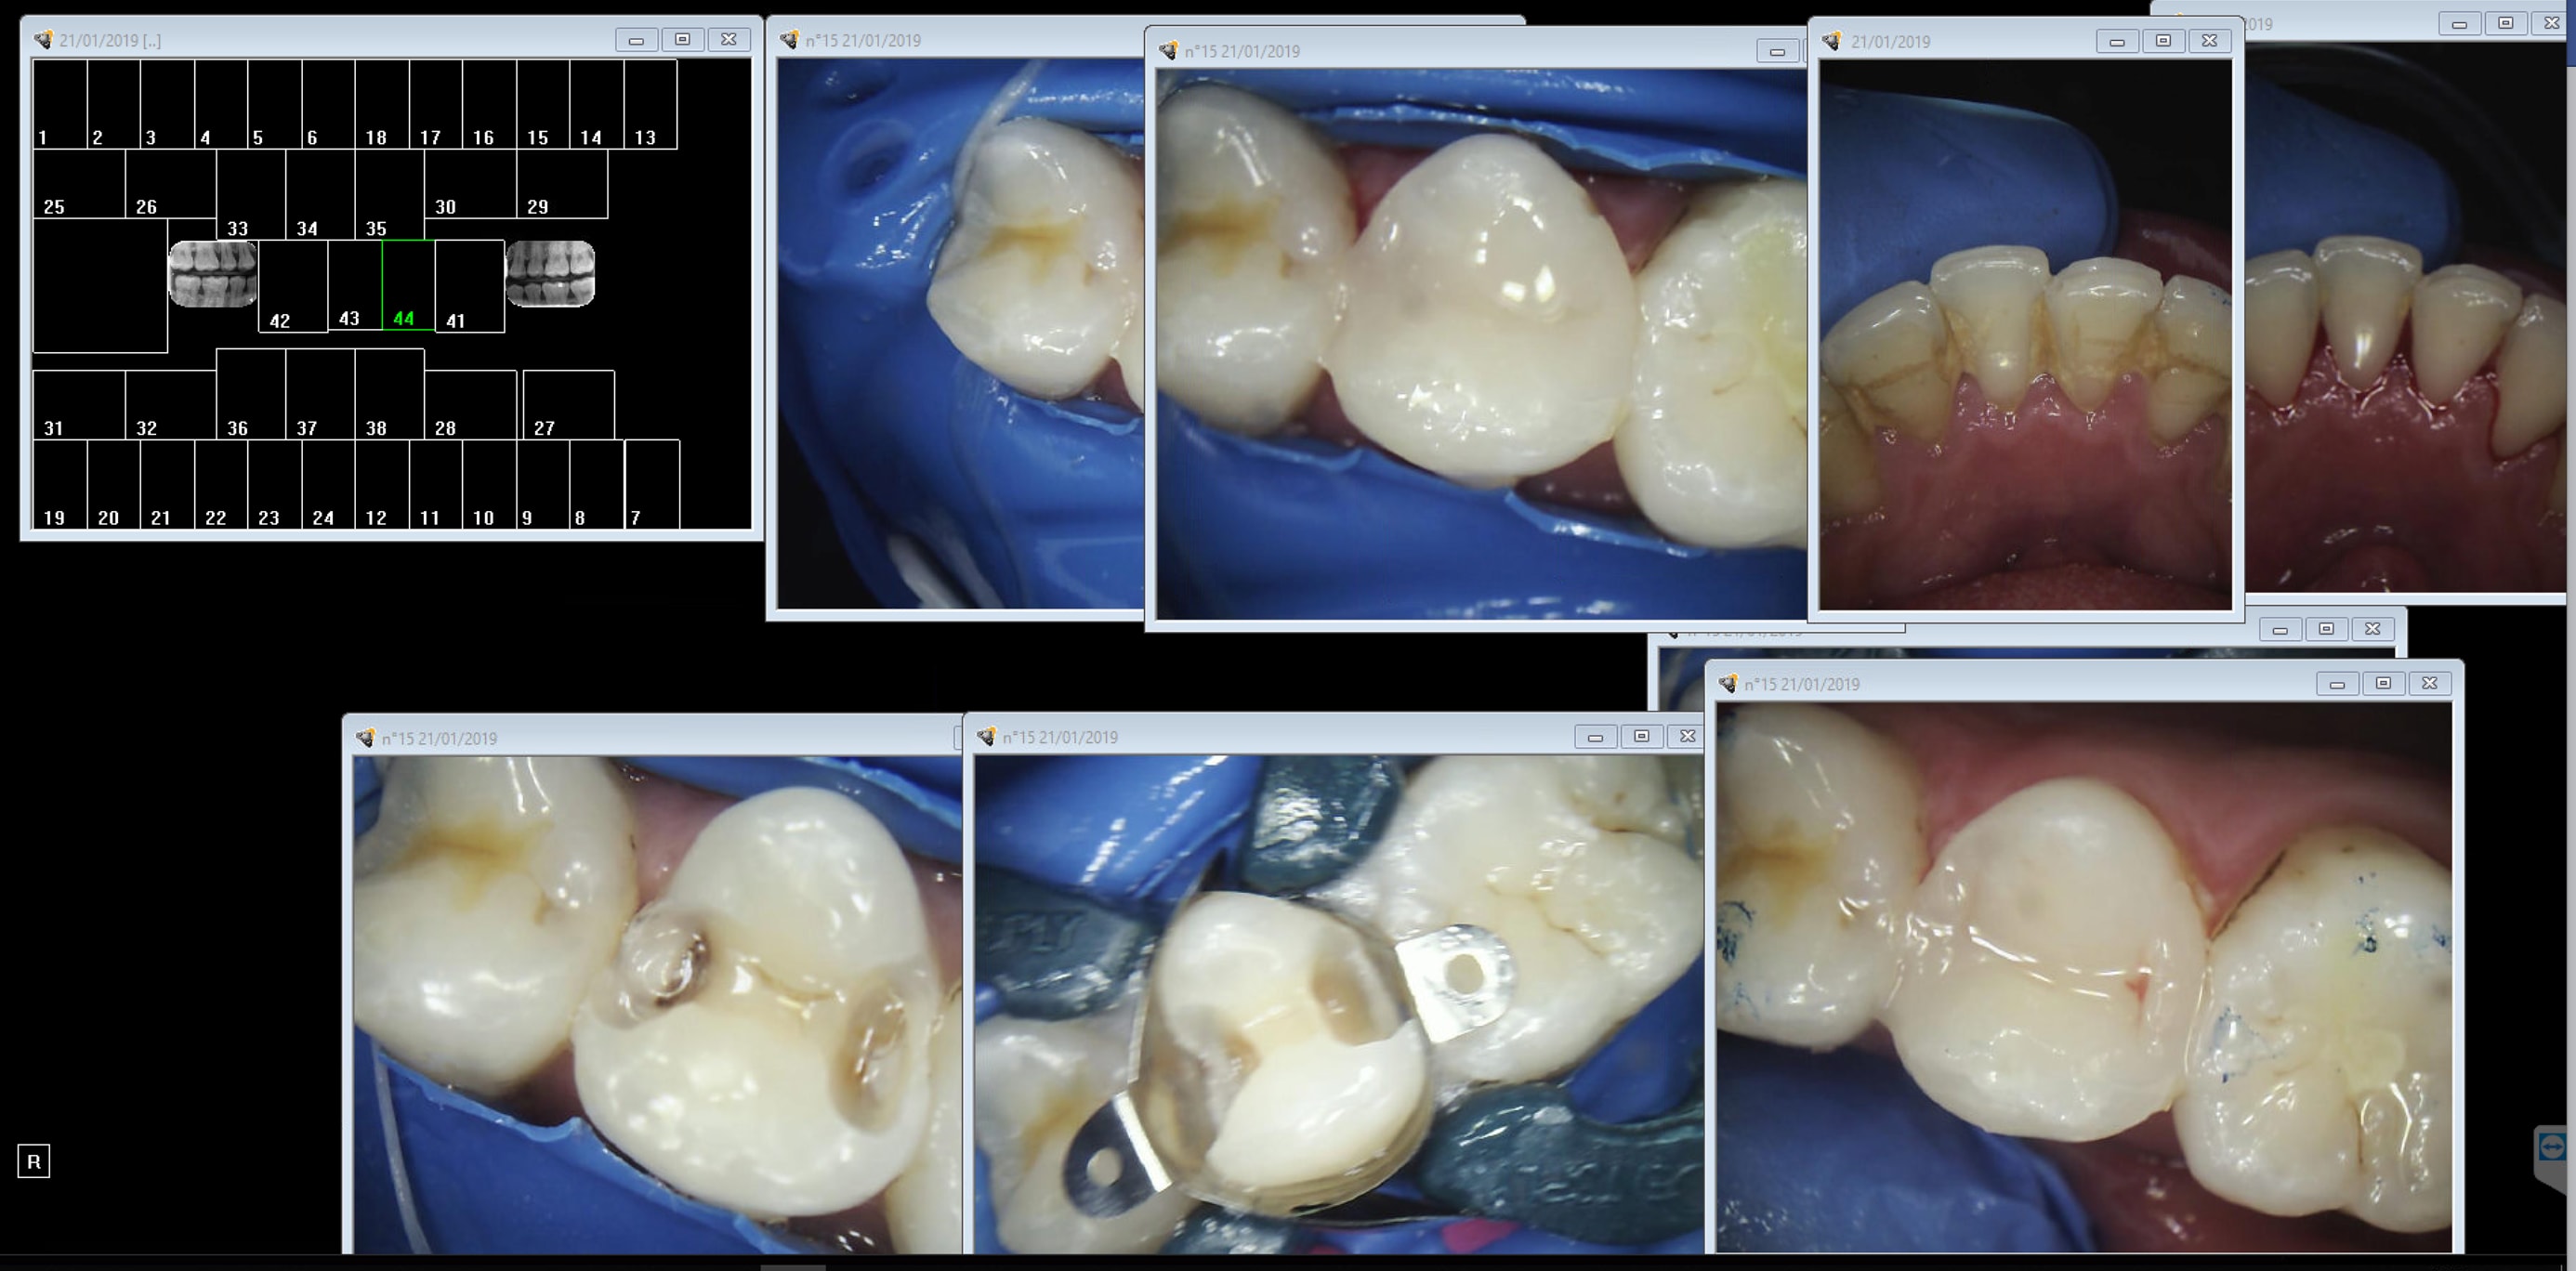

alors ç est quoi ce bordel ici ?

y en a encore qui cherchent des histoires à ma Casa ?

mais qu 'est ce tu leur as raconté encore ?, Casa ? ( pas tout lu ) . que t étais une grosse cochonne ( de dentiste ) qui travaille sans latex ? :-)

Comment ça ca existe des dentistes conventionnés qui ne posent pas la digue ? Je tombe des nues. -)))

Pour moi, ne pas respecter les obligations qui incombent au chirurgien dentiste, c'est collaborer avec ce système qui tire la profession vers le bas.

Ne pas mettre la digue, c'est aucunement une forme de résistance a quoi que ce soit.

C'est justement baisser la tête face a des honoraires qui ne permettent pas de bien travailler.

Et pas pour faire plus d'argent mais pour mieux soigner.